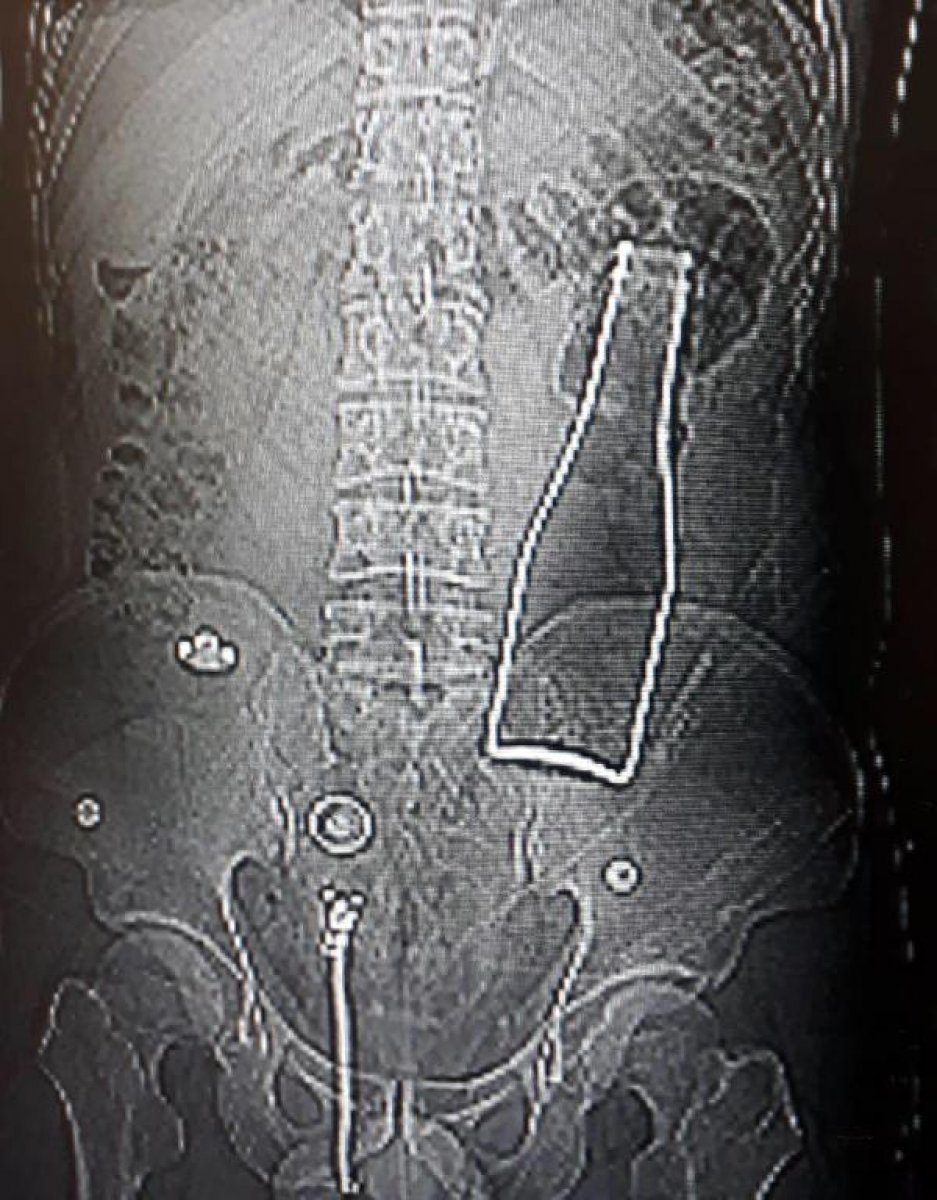

Röntgende görülen görüntü doktorları şaşırttı. Afganistan uyruklu A.E. 'nin karnında kalın bağırsağında bir şişe olduğu ortaya çıktı.

Yapılan kontrollerde şişenin A.E. isimli kişinin makatından girdiği tespit edildi.

AMELİYATA ALINDI

Bu durumun fark edilmesi sonrası A.E. isimli kişi hemen ameliyata alındı. Yaklaşık 1 saat süren ameliyat sonrası A.E. ifade verdi ve olayla ilgili açıklama yaptı.